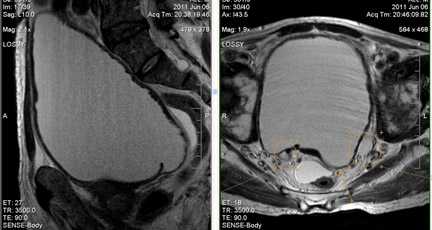

Дивертикулы мочевого пузыря.

Это локальное выпячивание стенки мочевого пузыря. Преобладают у мужчин, частота их встречаемости увеличивается с возрастом.

Развивается дивертикул, как правило, на фоне длительного повышения внутрипузырного давления при инфравезикальной обструкции (доброкачественная гиперплазия, рак предстательной железы, стриктуры уретры). Существует высокий риск развития уротелиального рака в дивертикуле мочевого пузыря за счет задержки в нем канцерогенных веществ.

При больших размерах дивертикулов показано оперативное лечение. По данным МРТ определяется локализация, размеры и осложнения дивертикула (воспаление или развитие опухоли).

а) Т2-сагиттальное изображение б) Т2-аксиальное изображение.

Истончение стенки и увеличения объема мочевого пузыря на фоне хронической инфравезикальной обструкции (вследствие ДГПЖ). Видна трабекулярность стенки мочевого пузыря, дивертикул задней стенки мочевого пузыря слева (б), стрелка; двусторонняя уретерэктазия.